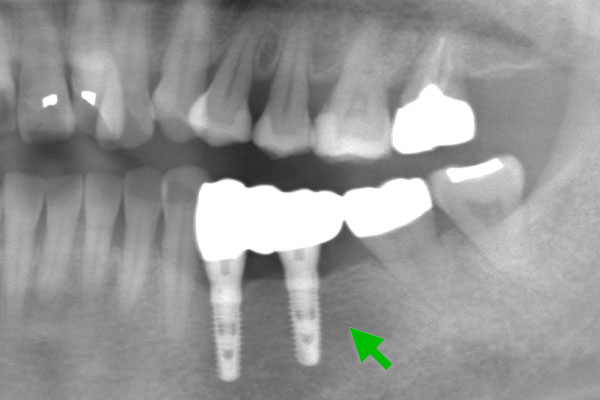

Case2.

| 主 訴 | 歯がない部分を治療したい |

|---|---|

| 治療期間 | 約4ヶ月 |

| 治療費 | 合計836,000円(税込) |

| 治療内容 | 治療1回目 CT撮影にて顎の骨にインプラントが入ることを確認し、サージカルガイドの型取り 治療2回目 インプラントを入れる治療 治療3回目 縫合してある糸をとり、周りをクリーニング 治療4回目 インプラントに土台を立てる治療 治療5回目 上部構造(被せ物)の型取り 治療6回目 上部構造(被せ物)をセット |

| 治療のリスク | インプラントの手術の後は腫れ、 痛みが出ることがあります。 インプラントの上部構造のセラミックは 稀に欠けることがあります。 |